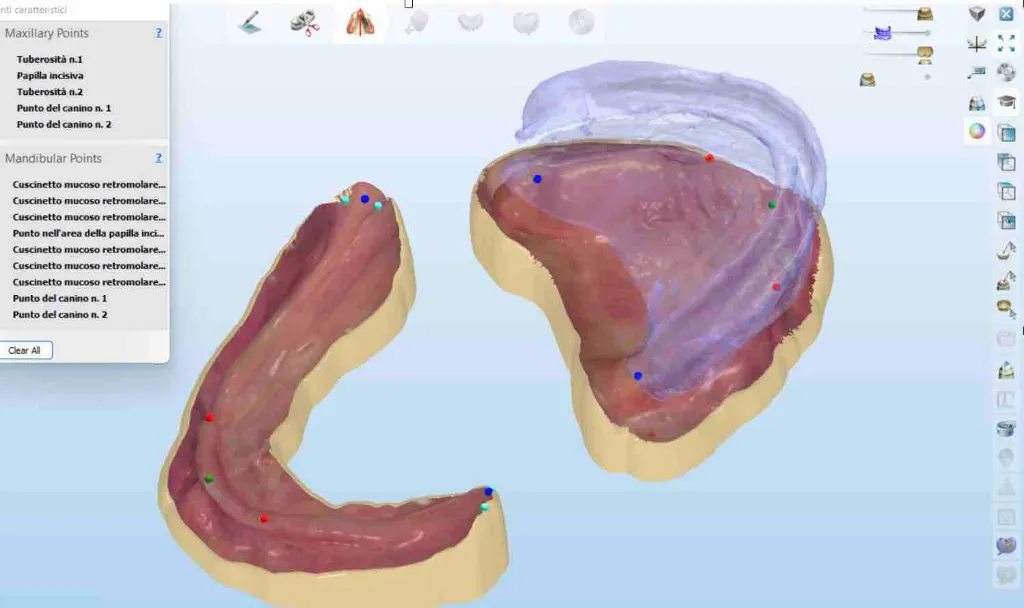

• Scansione intraorale di arcate edentule

• Flussi digitali per riabilitazioni implantari estese